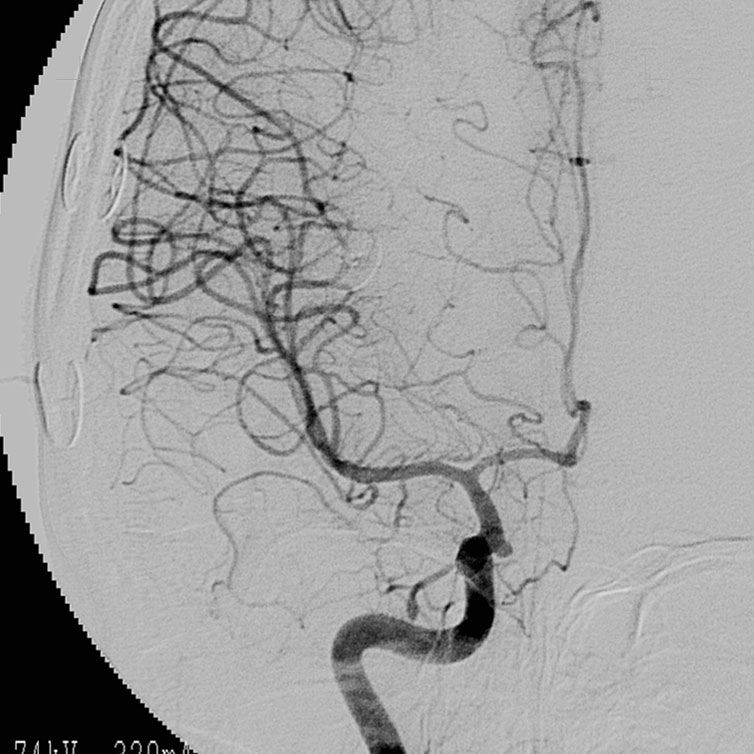

脳動脈瘤手術

脳動脈の瘤(動脈瘤)(図3)はある日突然破裂し、くも膜下出血を発症します。くも膜下出血は全体のおよそ30%が亡くなってしまう予後不良な病気です。症状は突然の激しい頭痛で通常嘔吐も伴います。

脳動脈瘤の治療は開頭術による脳動脈瘤頚部クリッピング術と血管内手術による脳動脈瘤塞栓術がありますが、現状ではクリッピング術が主流です。当科では破裂脳動脈瘤はもちろんのこと未破裂脳動脈瘤に対しても積極的に外科的治療を行っています。手術を行うにあたっては安全にかつ、確実に手術を行うことが是大前提です。そこで当科では以下にのべる工夫を行い、手術合併症を限りなくゼロになるように日々努力しています。